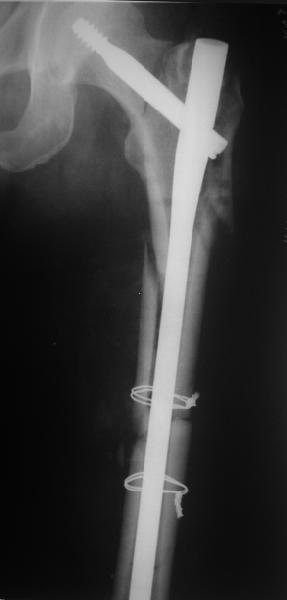

В общем, сделали. См. приложение.

Длина и из-за этого ось получились не совсем такие, как хотелось бы, все-таки срок после той операции уже 6 недель. Может быть, стоило провести дистракцию аппаратом неделю-другую. Заранее спасибо за комментарии и критику.